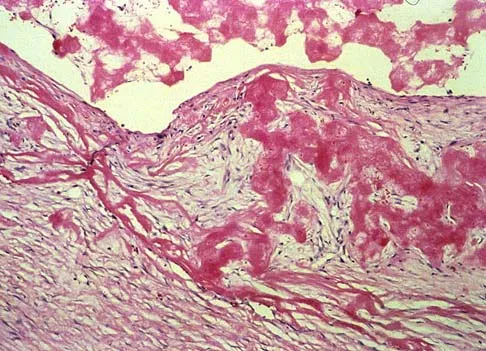

A 16-year-old boy has had thigh pain for the past several months. He denies any history of trauma. Examination reveals a large, deeply fixed, soft-tissue mass in the thigh. Laboratory results show an elevated erythrocyte sedimentation rate (ESR) and leukocytosis. A plain radiograph and MRI scan are shown in Figures 1a and 1b. Biopsy specimens are shown in Figures 1c and 1d. What is the most likely diagnosis?

Explanation